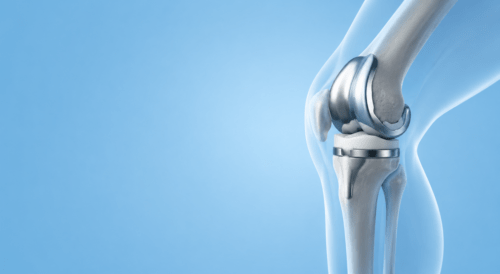

Що робити, якщо після операції на коліні залишився набряк?

Коли можна повернутися до спорту після операції на коліні?

Як відновитися після пластики передньої хрестоподібної зв’язки?

Коли можна ходити після операції на колінному суглобі?